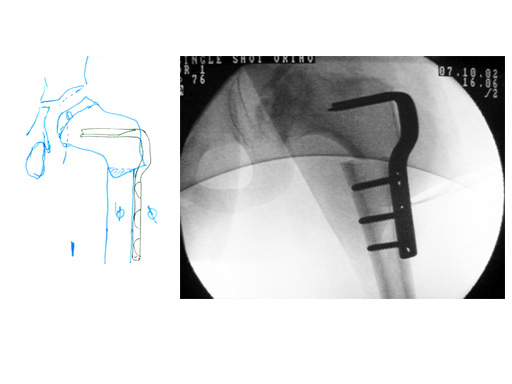

6-year-old boy with Legg-Calv-Perthes disease, postoperative x-ray.